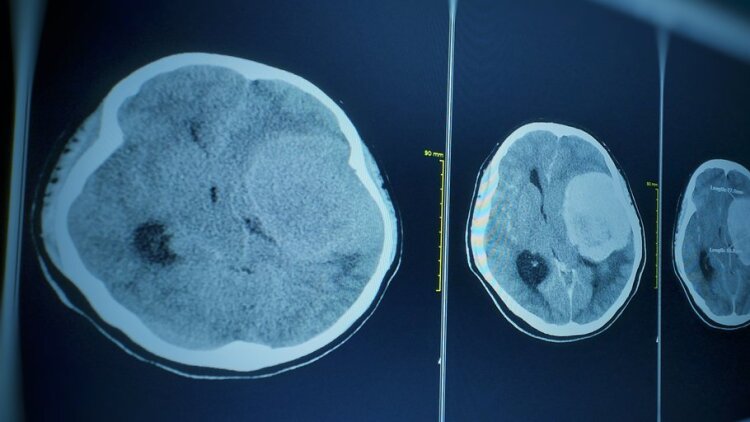

Το θύμα, που δεν είχε υποκείμενα νοσήματα, πέθανε από νεγλαιρίαση – γνωστή επίσης ως πρωτογενής αμοιβαδική μηνιγγοεγκεφαλίτιδα (primary amoebic meningoencephalitis ή PAM) – μια σπάνια λοίμωξη του εγκεφάλου, η οποία προκαλείται από την αμοιβάδα Naegleria fowleri.